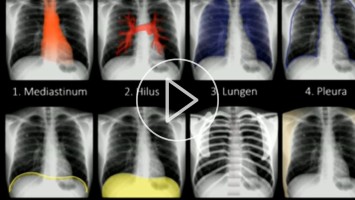

Röntgen-Thorax: die Bilder richtig deuten

Die am zweithäufigsten benötigte Röntgen-Aufnahme stellt der Röntgen-Thorax dar. PD Dr. Pregler geht im Video systematisch die notwendigen Schritte der Bildanalyse durch – vom Mediastinum bis zu den Weichteilen. Dabei benennt er wichtige Kenngrößen und gibt einige Fallbeispiele.